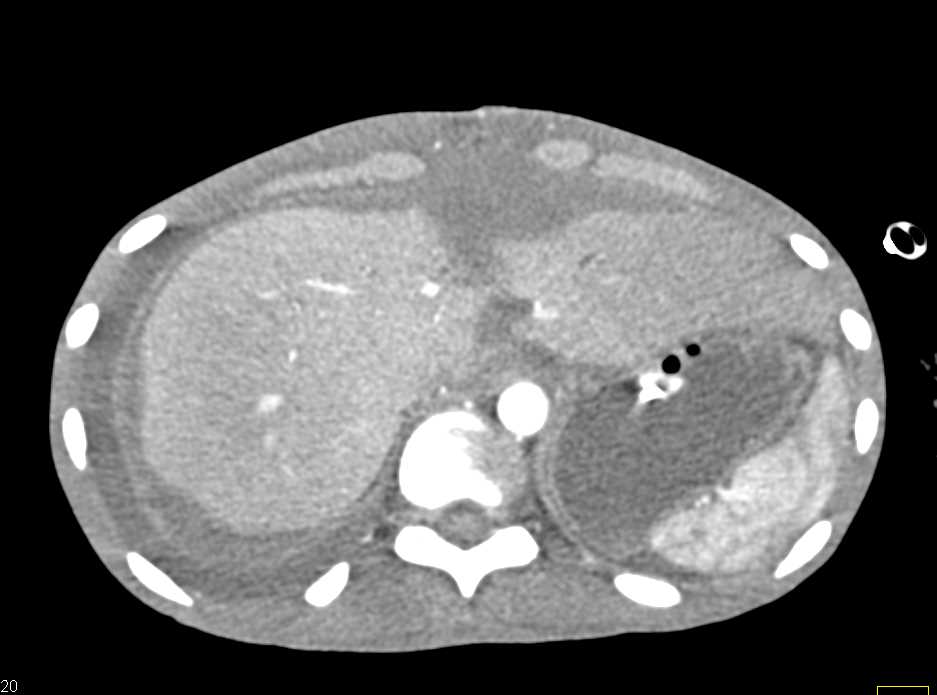

Transjugular Intrahepatic Portosystemic Shunt (TIPS) Catheter